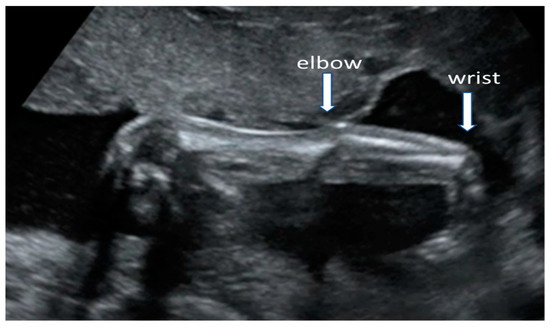

4.2. Early Anomaly Scan 16–18 Weeks

- Polizzi, A.; Huson, S.M.; Vincent, A. Teratogen update: Maternal myasthenia gravis as a cause of congenital arthrogryposis. Teratology 2000, 62, 332–341. [Google Scholar] [CrossRef]